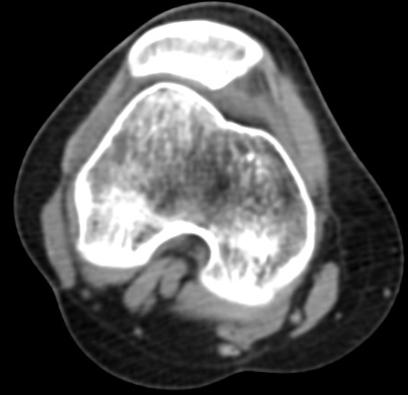

髌骨脱位不同于膝关节股骨与胫骨间的关节脱位。髌骨脱位发生在髌股关节。但是髌骨脱位的治疗并非简单的推回去复位即可。

髌骨脱位绝大部分是由先天性发育的因素引起,如果不做矫正,脱位会发生得越来越频繁,越来越容易。

随着运动医学的发展,髌骨脱位手术目前都是关节镜微创手术,一般只需在关节周围开2个5毫米的小孔,具有创伤小、出血少、安全性高、恢复快等优势。